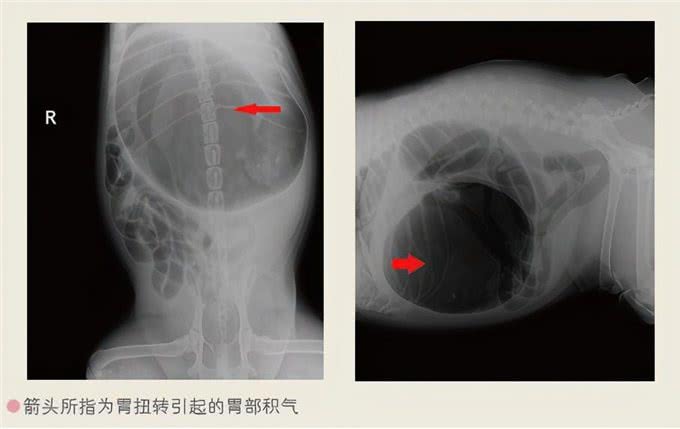

胃扭转扩张胃扭转扩张是指胃伴有以肠系膜为轴的旋转并发生扩张的病症。

治疗

手术前进行输液,保证血压正常,防止休克,严重者及时进行手术治疗,术后输液疗法,抗菌消炎。

专家指导

发病率高的犬可以提前做胃固定手术,不要让犬在过度饮水、饮食后剧烈运动,食盆不要放置过高,饲喂时避免发生应激反应。